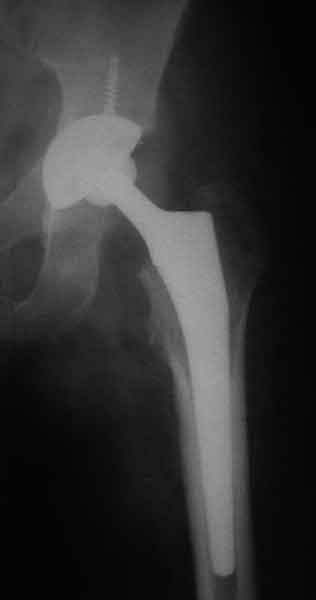

Еще пара фото, ситуация несколько иная, задачи те же, открытое вправление застарелого вывиха в 2002, молодой возраст. Сейчас госпитализирована для эндопротезирования.

Больного прооперировали на прошлой неделе (цементный протез, цемент с гентамицином). Использовали задне-боковой доступ. В области перелома подвижности практически не было, так что тему сообщения уместно заменить на "неправильно сросшаяся шейка". И в головке, и во впадине

были значительные дегенеративные изменения, так что ни биполяр, ни остеосинтез тут неуместны (хотя это предлагали в ortopod'е). После релиза удлинили ногу на 3 см. Дальше удлинять побоялись из-за

натяжения седалищного нерва, хотя в принципе можно было бы еще 15-20 мм нарастить. По послеоперационной рентгенограмме анатомическое укорочение порядка 15 мм. Клинически при ходьбе - 4 см, но это за счет перекоса таза.

The patient underwent cemented THR on last week. Postero-lateral approach was used. There was only minimal motion at the fracture site and we had to cut the femoral head with oscillating saw. The femoral head was deformed with it's cartilage completely absent in some areas.

Acetabulum showed gross degenerative changes, especially in superior rim. So I think it was right choice not to do ORIF in this case. After some soft tissue release we've lengthened the leg up to 3 cm. Further lengthening was possible but we stopped at that moment due to tension of n. ischiadicus. Now patient walks with crutches. Leg length discrepancy is about 4 cm due to pelvic tilt (discrepancy on post-op x-ray is 15 mm).